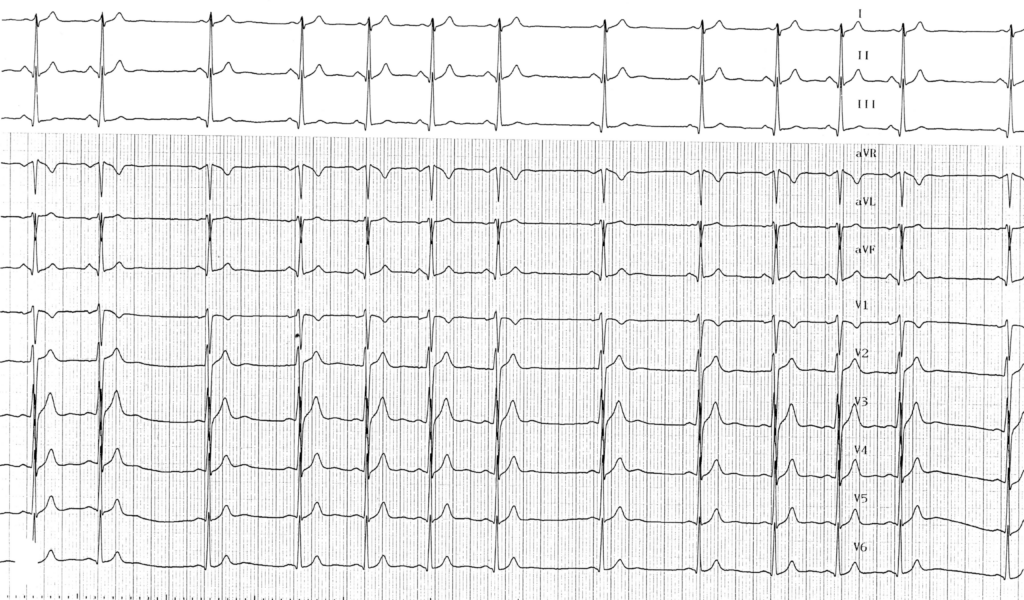

Sur l’électrocardiogramme, l’arythmie sinusale respiratoire phasique se traduit par un rythme à commande sinusale dont la fréquence est nettement irrégulière. On retrouve donc:

• Des ondes P identiques sans modification de morphologie;

• Une irrégularité des ondes P présentant des écarts de plus de 160 ms entre les intervalles PP;

• Les variations de durée des cycles PP sont périodiques et suivent les cycles respiratoires; une accélération du rythme sinusal est observée à la fin de l’expiration (reprise du tonus vagal) alors qu’un ralentissement du rythme sinusal survient à la fin de l’inspiration et au début de l’expiration (baisse du tonus vagal); ces variations disparaissent lors des apnées et diminuent lors d’un effort avec l’augmentation de la fréquence cardiaque;

• L’intervalle PR et le reste de l’électrocardiogramme sont généralement normaux;